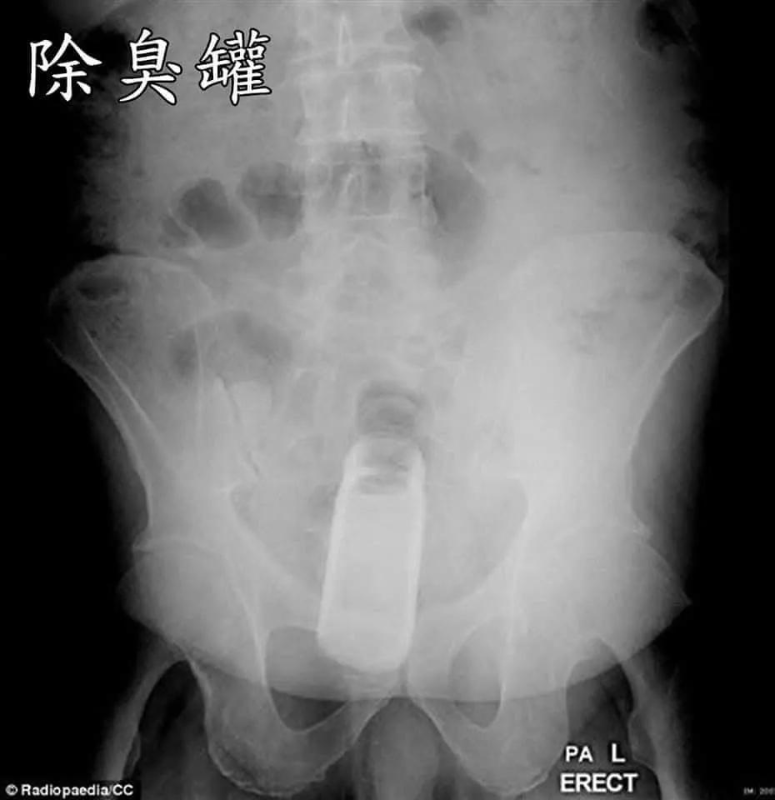

醫生公開「年度直腸內最怪案例」

醫師“衛教宣導”:拜託大家,屁眼是“消化器官”不是“性器官”,請不要為了“性樂趣

”,亂塞異物進入肛門!謝謝!!

https://i.imgur.com/pVOs0dg.jpeg 除臭瓶

![[圖]](https://imgur.disp.cc/4d/pVOs0dg.jpeg)